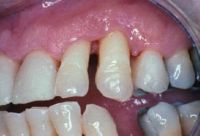

En este caso, el paciente presenta una destrucción periodontal grave del segmento anterior maxilar izquierdo que incluye los incisivos y el canino. El incisivo lateral y el canino tienen un grado 2 de movilidad y una pérdida de masa ósea de más del 60%. El paciente se queja de dolor durante la masticación e incomodidad en los dientes la mayor parte del tiempo.

Se tomó la decisión de ferulizar utilizando composite y la fibra de refuerzo Ribbond. Se realizó este tratamiento debido a la ajustada oclusión y a la necesidad de mantener los contactos oclusales. También, era aconsejable una férula en vestibular porque las fuerzas de oclusión se ejercían sobre la superficie de adhesión.

Se realizó un raspado radicular. Tras la finalización de la terapia inicial periodontal, se llevó a cabo el tratamiento para ferulizar los incisivos y caninos por el traumatismo oclusal secundario.